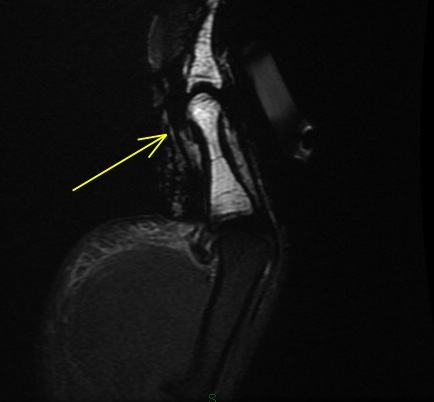

Figure 1 for case Flexor pollicis longus tendon ( RID2383 ) laceration

Figure 1